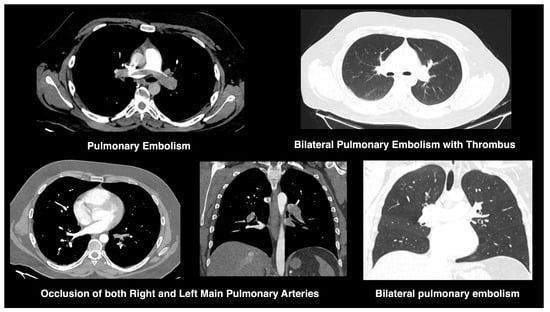

All chest CT scans were assessed for characteristic imaging features (Figure 1), including consolidation, ground-glass opacities, nodular lesions, lymphadenopathy, vascular thickening, and evidence of embolism (Figure 2). To quantify lung involvement, we used a semi-quantitative pulmonary damage severity index based on estimated parenchymal involvement in each of the five lung lobes. Each lobe was scored from 0 (no involvement) to 5 (more than 75% involvement), yielding a total score ranging from 0 to 25 per patient. This approach, previously validated in similar contexts [,], was selected over standardized diagnostic scoring systems such as CO-RADS or RALE due to its flexibility and broader applicability in comparative viral pneumonia analysis. Lymphadenopathy was defined as lymph nodes with a short-axis diameter greater than 1 cm. Vascular thickening was identified by abnormal vessel enlargement—either greater than nearby vessels in unaffected areas, larger than corresponding vessels in the contralateral lung, or demonstrating a lack of tapering toward the periphery.

Figure 2.

CT findings of pulmonary embolism in COVID-19. CT angiograms demonstrate bilateral pulmonary embolism, with thrombus visualized in both main pulmonary arteries. Findings include vascular occlusion and associated parenchymal ground-glass opacities, compatible with COVID-19-related embolic events.